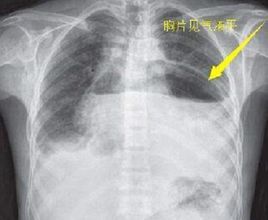

肺部積水的主要檢查方式有:漿膜腔積液細胞計數、胸部CT檢查、胸部B超檢查、支氣管造影、胸部MRI、肺活檢等。

肺積水診斷:外觀漏出液透明清亮,靜置不凝固,比重<1。016~1。018。滲出液則多呈草黃色稍混濁,比重>1。018。膿性胸液若為大腸桿菌或厭氧菌感染常有臭味。血性胸液呈程度不同的洗肉水樣或靜脈血樣;乳狀胸液為乳糜胸;若胸液呈朱古力色應考慮阿米巴肝膿腫破潰入胸腔的可能;黑色胸液可能為曲菌感染。